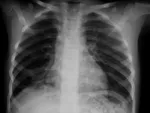

Atelektazi

Atelektazi nedir ?

Ciğer dokularının çökmesi sonucu ciğerin havasız kalmasına yol açan bir durumdur.